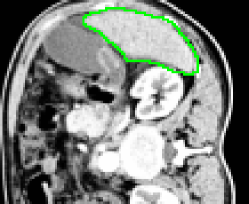

4.1 Metrication artifacts and minimal surfaces

We begin by comparing the CCMF segmentation result with the classical max-flow algorithm (graph cuts). Figure 3 shows the segmentation of a brain, in which the contours obtained by graph cuts are noticeably blocky in the areas of weak gradient, while the contours obtained by both AT-CMF and CCMF are smooth.